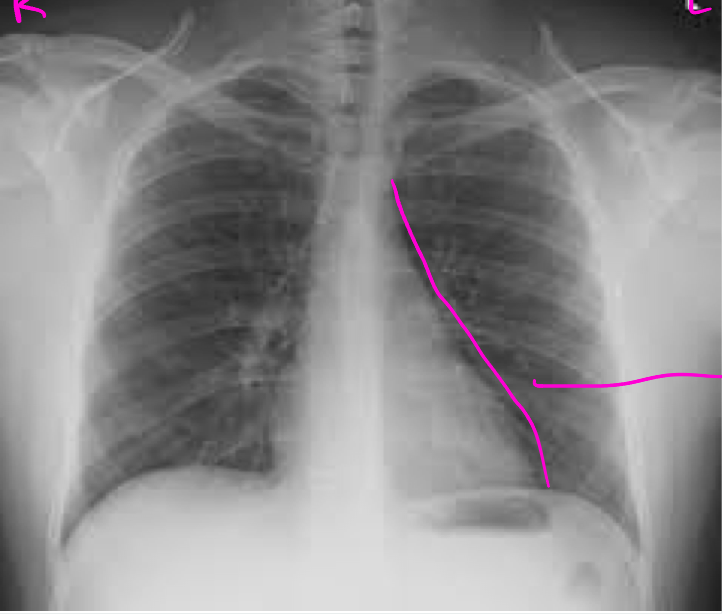

CXR- due to different densities of internal structures

can get a detailed exam of the lung parenchyma, pulmonary blood vessels, and of the heart